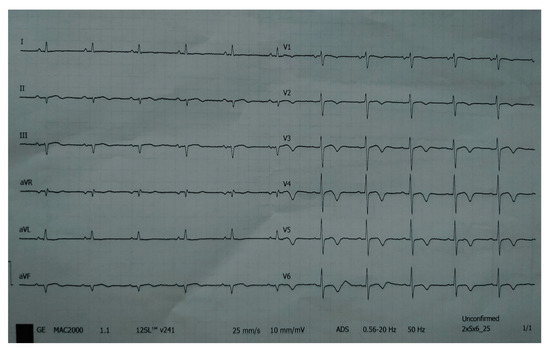

A 78-year-old woman was admitted to the general hospital due to chest pain and ECG signs of acute inferior STEMI. She had experienced chest pain 36 h prior to the admission, following a period of intense emotional stress. The patient also had anxiety as a comorbidity. Upon admission, the patient was alert and orientated, hemodynamically and rhythmically stable, and without signs of heart failure. It was concluded that the patient was a late presenter of myocardial infarction, since 36 h had passed from the beginning of the symptoms. As a result, she did not receive primary percutaneous coronary intervention, nor was she given fibrinolytic therapy. Two days after admission, the patient reported intense chest pain. The ECG registered diffuse ST-segment elevation with ST-segment denivelation in aVR and QTc interval (406 ms) (Figure 1).

Figure 1.

ECG registered diffuse ST-segment elevation with ST-segment denivelation in aVR and QTc interval (406 ms).

On the eighth hospital day, the patient was asymptomatic, hemodynamically and rhythmically stable, and without signs of heart failure. The ECG showed a negative T-wave in the anterior leads (Figure 13). She was discharged with acetylsalicylic acid, Ticagrelor, Bisoprolol, Ramipril, a statin, and a proton pump inhibitor.

Figure 13.

ECG registered negative T-wave in anterior leads.